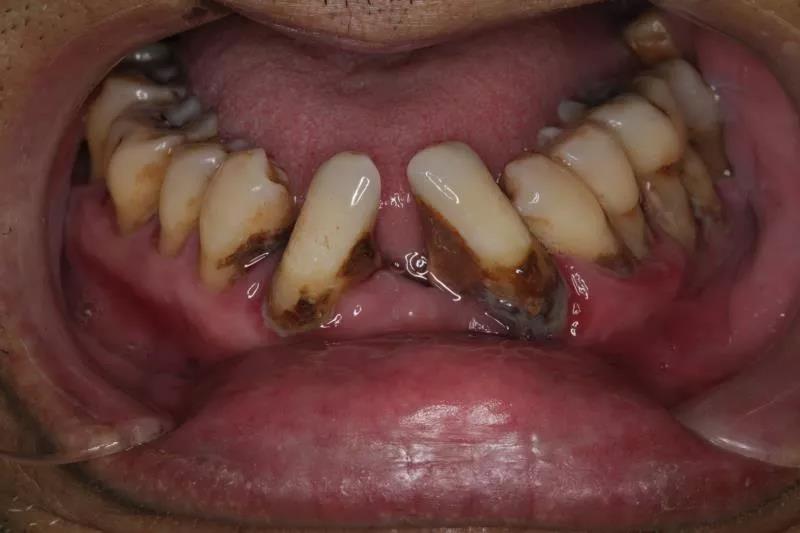

发展到现在,康老师的上颌已经完全没有牙齿了,下颌的牙齿也因为牙龈萎缩,松动地很厉害。

康老师下颌的牙齿牙龈萎缩,并且因为上颌佩戴的是假牙,没有真牙对下颌牙齿产生的作用力,导致下颌牙齿变长,影响外观与正常的咀嚼。

康老师第一次来看牙时的口内照片